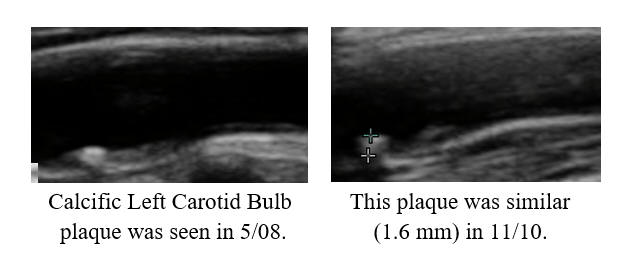

Cyclodextrin for IMT and Plaque Control when Cholesterol Control is Not Possible

I began working with PM in '07, 14 years ago. Chest tightness, then associated with a non-threatening stress test, resolved following 20 IV EDTA treatments. PM's IMT of 0.678 was below-average-for-age; carotid plaque was not identified. PM began a program of risk factor reduction, but we could not dent PM's LDL elevation (150-180 mg/dl), at least not with treatments that PM could tolerate. PM's IMT rose between '08 and '22, at an average rate of 0.007 mm per year, but calcific carotid bulb plaque had developed over this interval. PM received two months of cyclodextrin in '23, as a proactive preventative, our theory being that if we can't lower PM's circulating lipids, perhaps we could make up by pulling lipids out of the vascular wall. PM's IMT was repeated in 1/25, and demonstrated active IMT regression, at a rate of 0.02 mm per year (a lot). Thus PM's predisposition towards plaque formation was reversing, and of greater importance to PM, we observed plaque regression. The right carotid bulb plaque, which had developed over 14 years, decreased in size over two years! Our plan, going forward, will be for PM to complete two moths of cyclodextrin every year, with a repeat carotid study in 2-3 years.